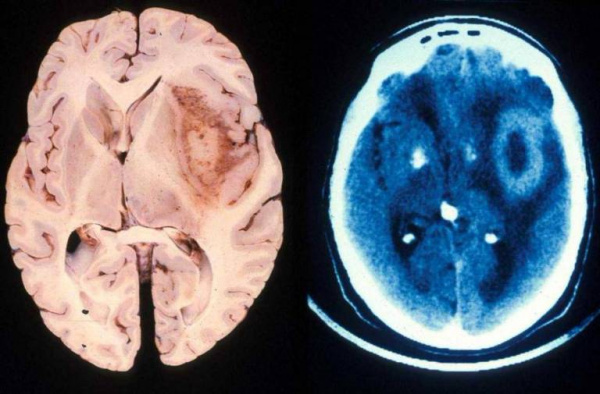

- Компьютерная томография. Выявляет изоденсное церебральное образование с гиподенсным участком центрального некроза, перифокальным отеком, геморрагическим компонентом. Характерен масс-эффект. КТ с контрастированием демонстрирует кольцевое неравномерное окрашивание. Микроскопическая инфильтрация обычно распространяется за пределы визуализируемого очага.

- Магнитно-резонансная томография. МРТ с контрастом гадолиния показывает образование неправильной формы с плотным кольцом усиления, некротизированным центром. Некроз считается отличительной чертой глиобластомы. Также могут визуализироваться окружающий образование вазогенный отек, кровоизлияния, кистозный компонент, искривление или смещение желудочков. Примерно в 13% случаев наблюдается многоочаговость поражения.

В клинической неврологии глиобластому дифференцируют с внутримозговой гематомой, абсцессом, лимфомой ЦНС, астроцитомой, артериовенозной мальформацией. Дифференциация проводится по результатам нейровизуализации. Отличительной особенностью глиобластомы является наличие некротизированного участка. Однако лимфома у пациентов со СПИД также имеет некротический компонент. В этом случае дифдиагностика осуществляется в ходе гистологического исследования биопсийного материала.